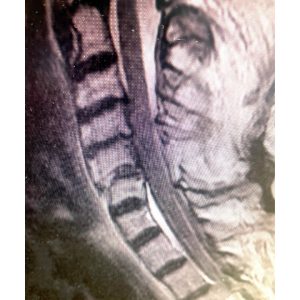

The first 2 pictures are a CT scan and then an MRI of the C5-6 fracture with spinal cord compression. The next is X-ray taken during surgery. The last is X-ray at 2 months postoperative. At 2 months after surgery, the patient is living at home again. She is as strong as ever!”